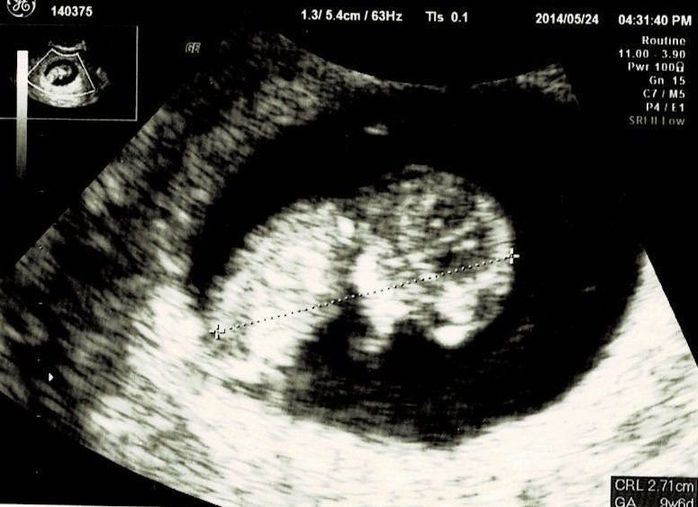

妊娠8週目エコー写真

前の月に生理が止まり、大急ぎで婦人科受診したら“ストレスが原因だっただけ”という出来事があったので、多少生理が遅れていても気にしないでいました。会社の打ち上げに参加した時、ほとんど飲んでいないのにひどく酔っ払ってしまい、体調に違和感を感じました。

翌日妊娠検査薬にトライ。陽性が出たので急いで産婦人科へ。今度こそ妊娠でした!喜びのあまり、この日に母子手帳を受け取りに行ったのを覚えています。